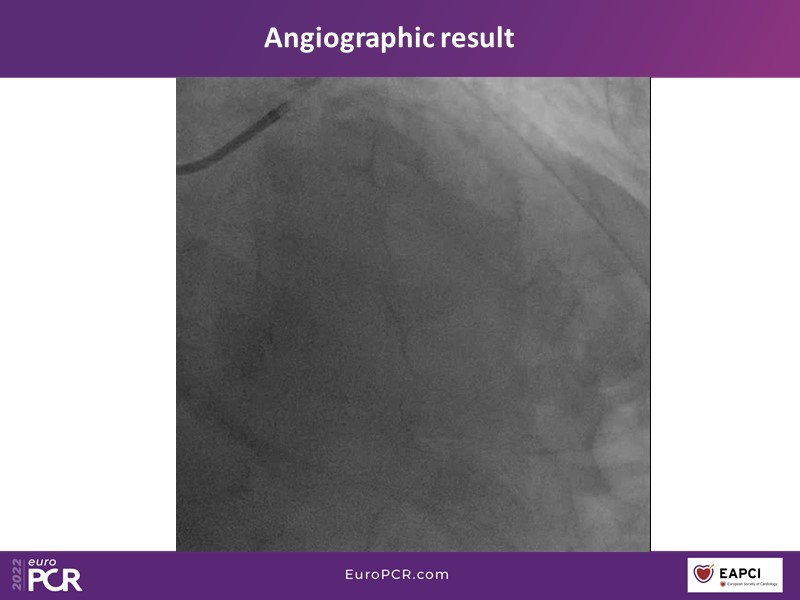

This EuroPCR 2022 session aims to show, based on real-life cases, that even complex coronary disease can be treated without the need for permanent coronary stents. Learn how to prepare the vessel, deliver the therapy, and assess immediate outcomes after "DCB-alone" PCI, discuss de novo, small vessels, and in-stent restenosis cases with follow-up, define what may be an optimal long-term result, refresh the scientific bases, and understand the clinical benefits and safety of paclitaxel DCBs.

- To know how to prepare the vessel, deliver the therapy and evaluate the immediate results after "DCB-alone" PCI

- To discuss de novo, small vessels and in-stent restenosis cases with follow-up and define what may be an optimal long-term result